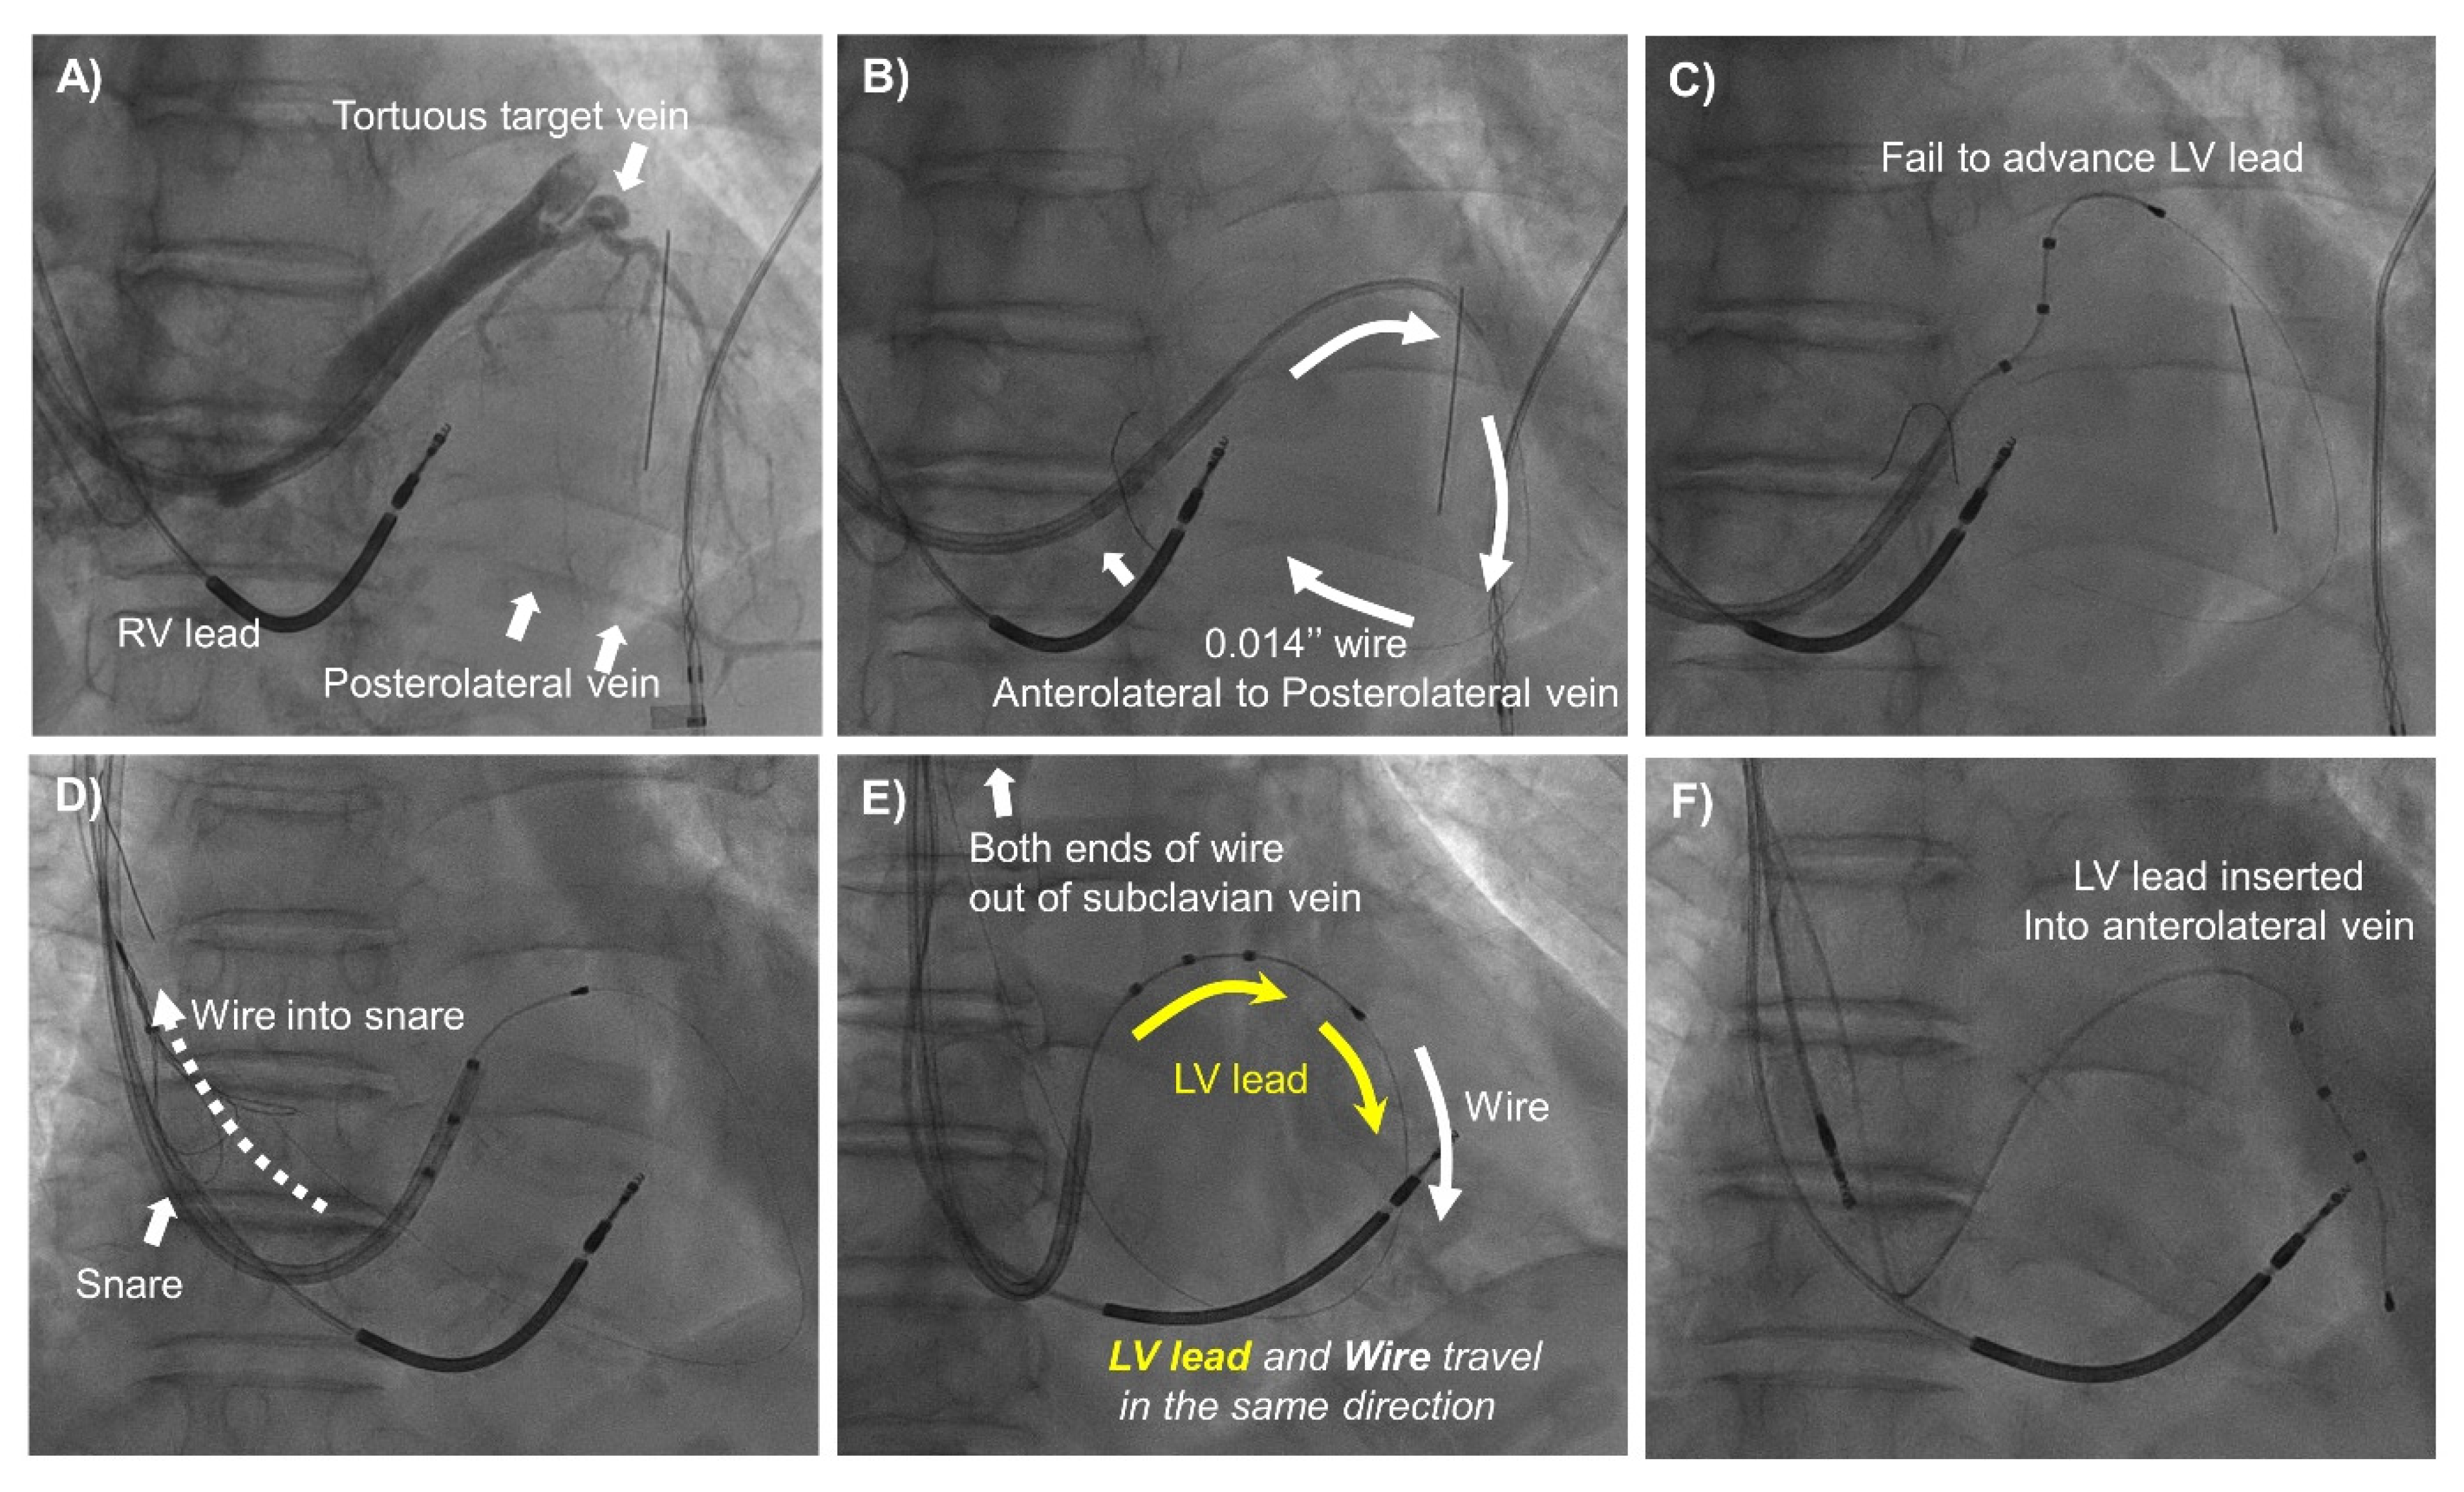

2.2. CRT Implantation and Snare Technique